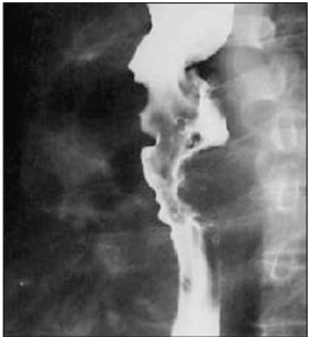

Um paciente de 71 anos de idade apresentou queixa de disfagia cervical, associada a deglutição ruidosa, regurgitação, abaulamento cervical esquerdo, acessos de tosse, halitose e emagrecimento progressivo há três anos. Ele, então, procurou o cirurgião de cabeça e pescoço para investigar essa sintomatologia, o qual optou pela realização de exames de imagem, que evidenciaram as imagens apresentadas.

Qual é a hipótese diagnóstica mais plausível?